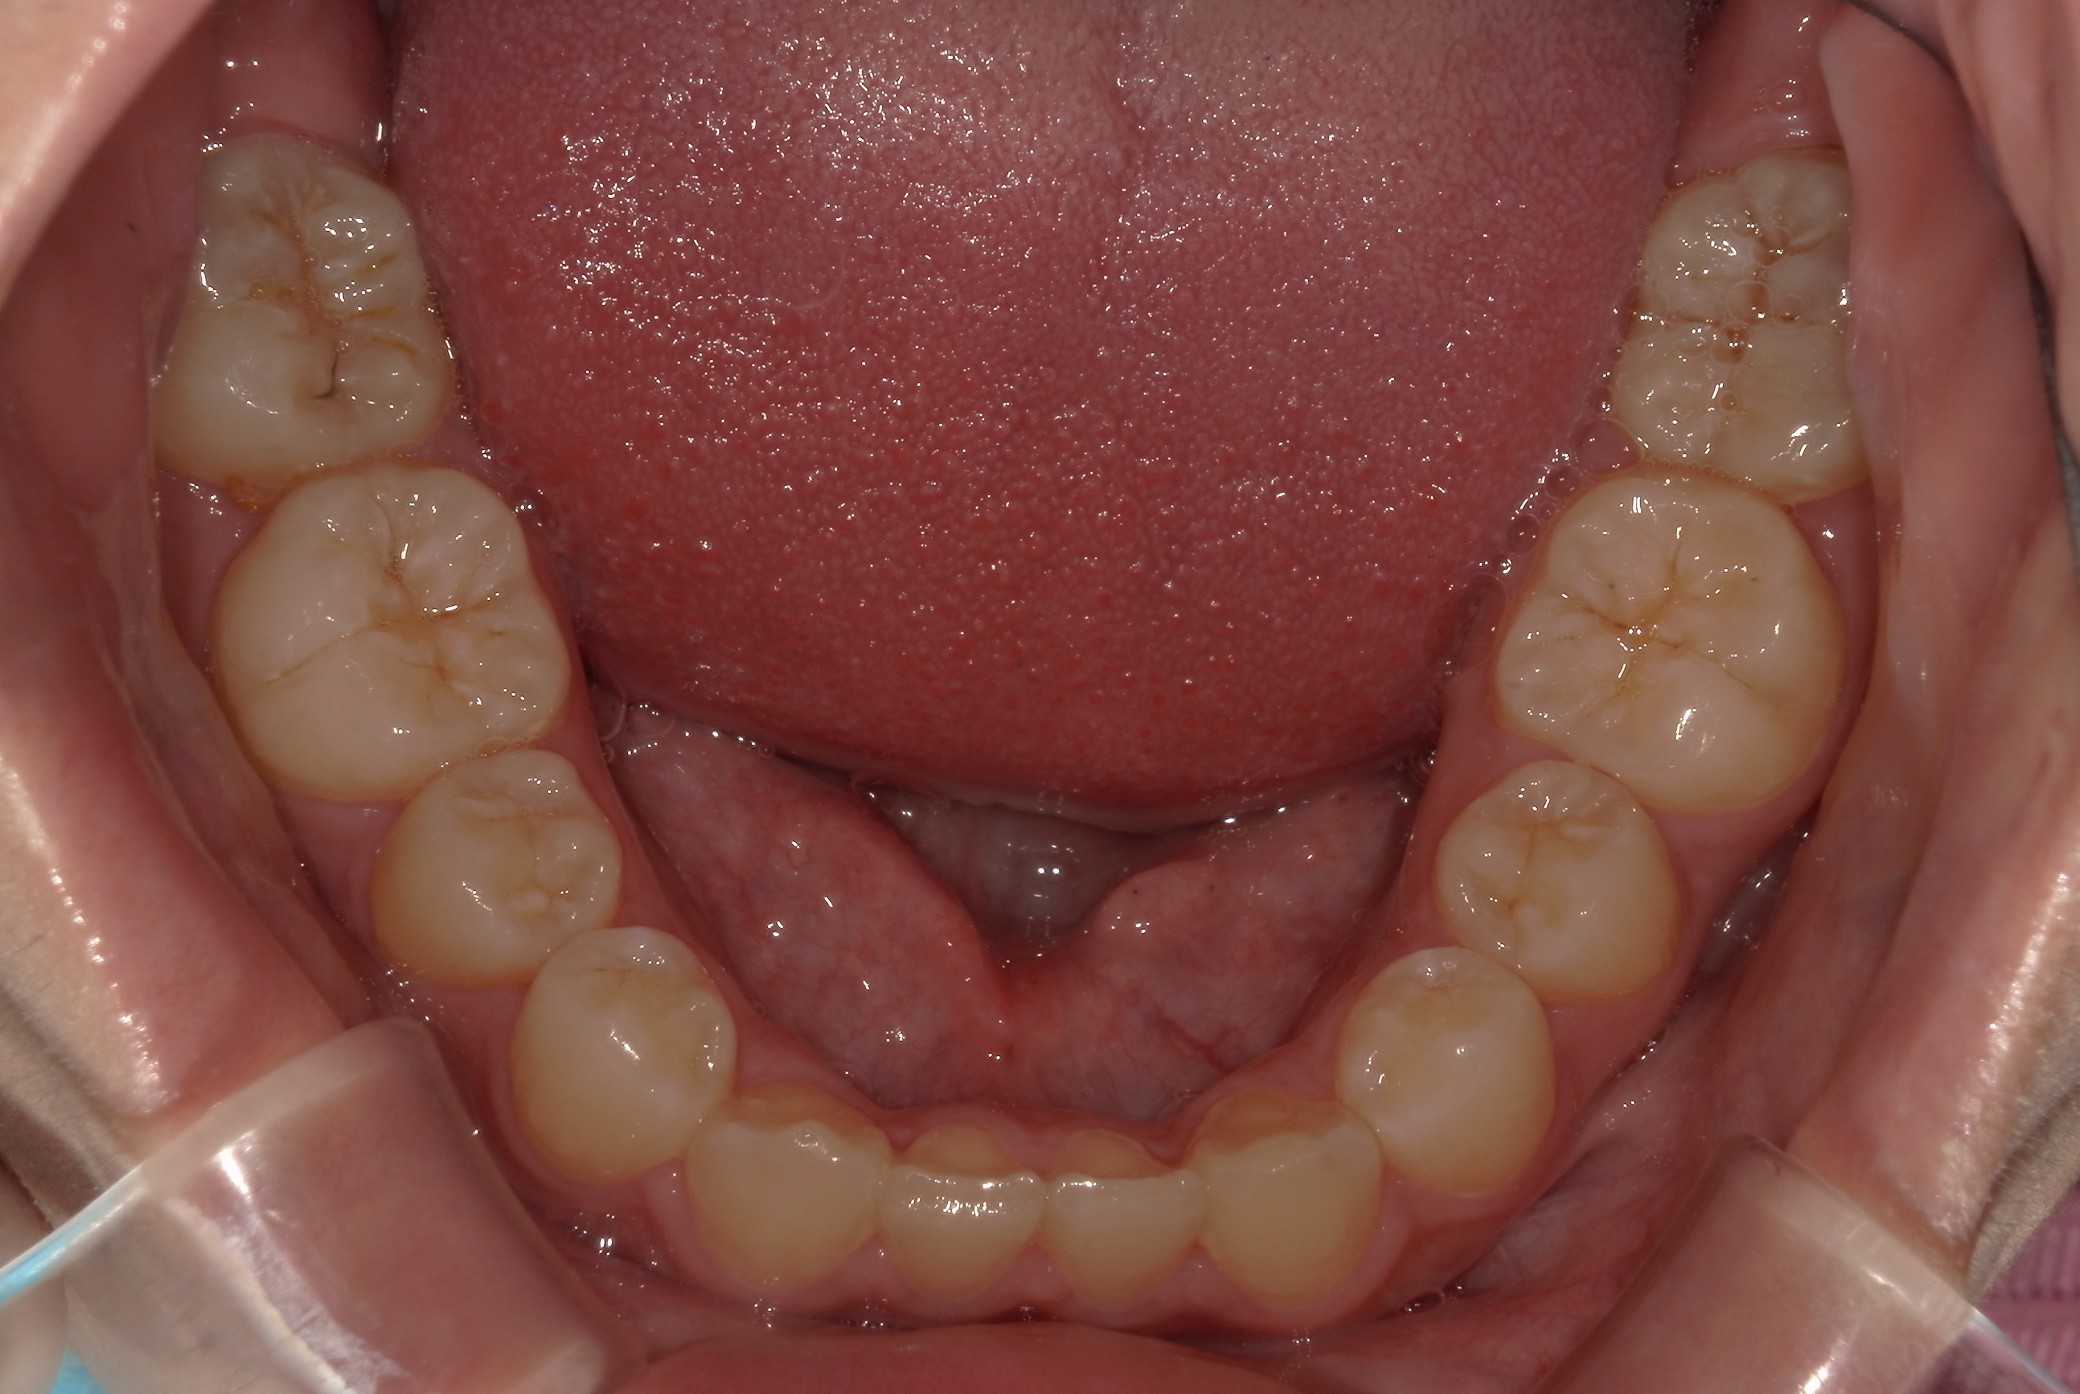

矯正術前:下顎

矯正術後:下顎